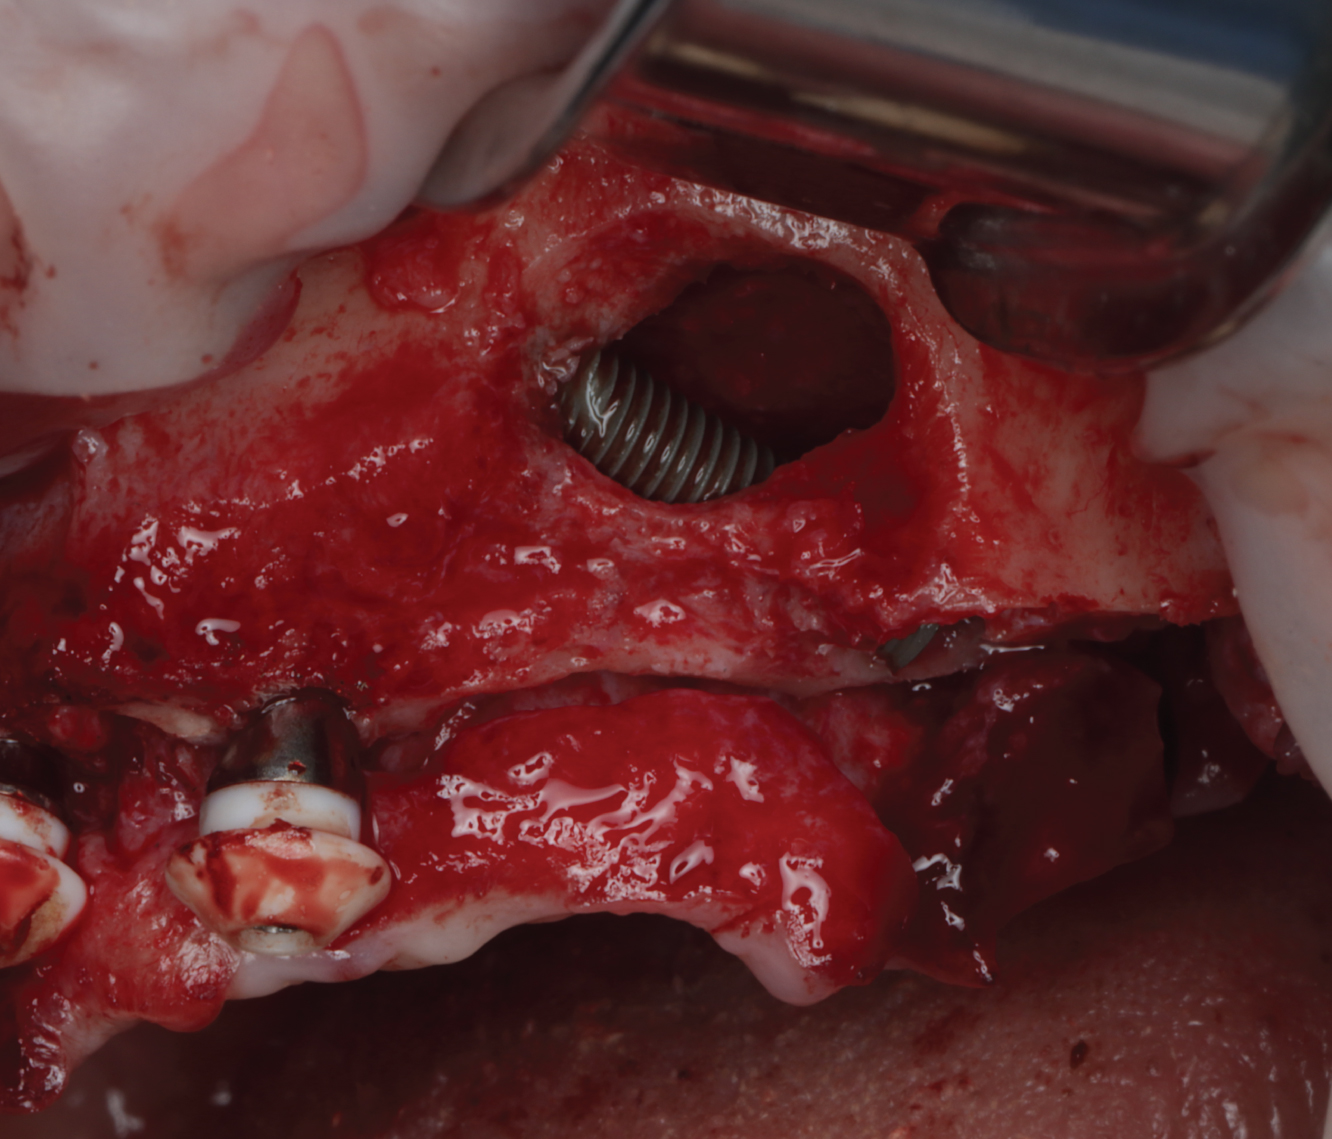

Director’s Clinical Cases

Director’s Clinical Cases